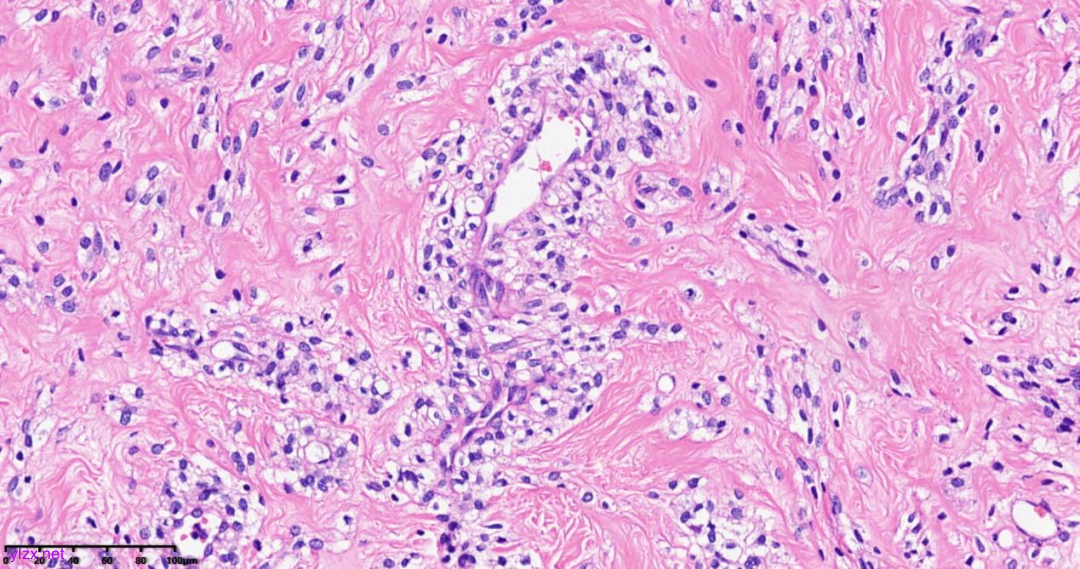

肿瘤细胞以梭形细胞、卵圆形细胞为主,部分为胞浆透亮的上皮样形态,透亮细胞界限较清,胞质淡染或胞浆丰富、嗜酸性,肿瘤内血管丰富,肿瘤细胞围绕血管周围片巢状、束状及放射状排列;肿瘤细胞核异型性不明显,核分裂像少见(<1个/50HPF),染色质开放,可见小核仁;肿瘤间质水肿、黏液变性,纤维胶原增生伴玻璃样变性。

图1~5 低倍镜下:肿瘤细胞以梭形细胞、卵圆形细胞为主,部分为胞浆透亮的上皮样形态,肿瘤细胞分布疏密不均,部分区密集丰富,部分区肿瘤细胞稀少,间质疏松水肿、黏液变性,肿瘤细胞围绕血管周围生长,局部间质纤维胶原增生伴玻璃样变性。

图6 中倍镜下:肿瘤内血管丰富,胞浆透亮的上皮样细胞围绕血管周围片巢状、束状及放射状排列。

图7~10 高倍镜下:梭形细胞、上皮样细胞组成的巢状、梁状结构,周围包绕纤细的薄壁毛细血管,肿瘤细胞呈放射状排列在血管周围,细胞界限较清,胞浆丰富、嗜酸性或透亮,细胞异型性不明显,核分裂像少见,细胞核呈圆形,染色质开放,可见小核仁;局部少量慢性炎细胞浸润。